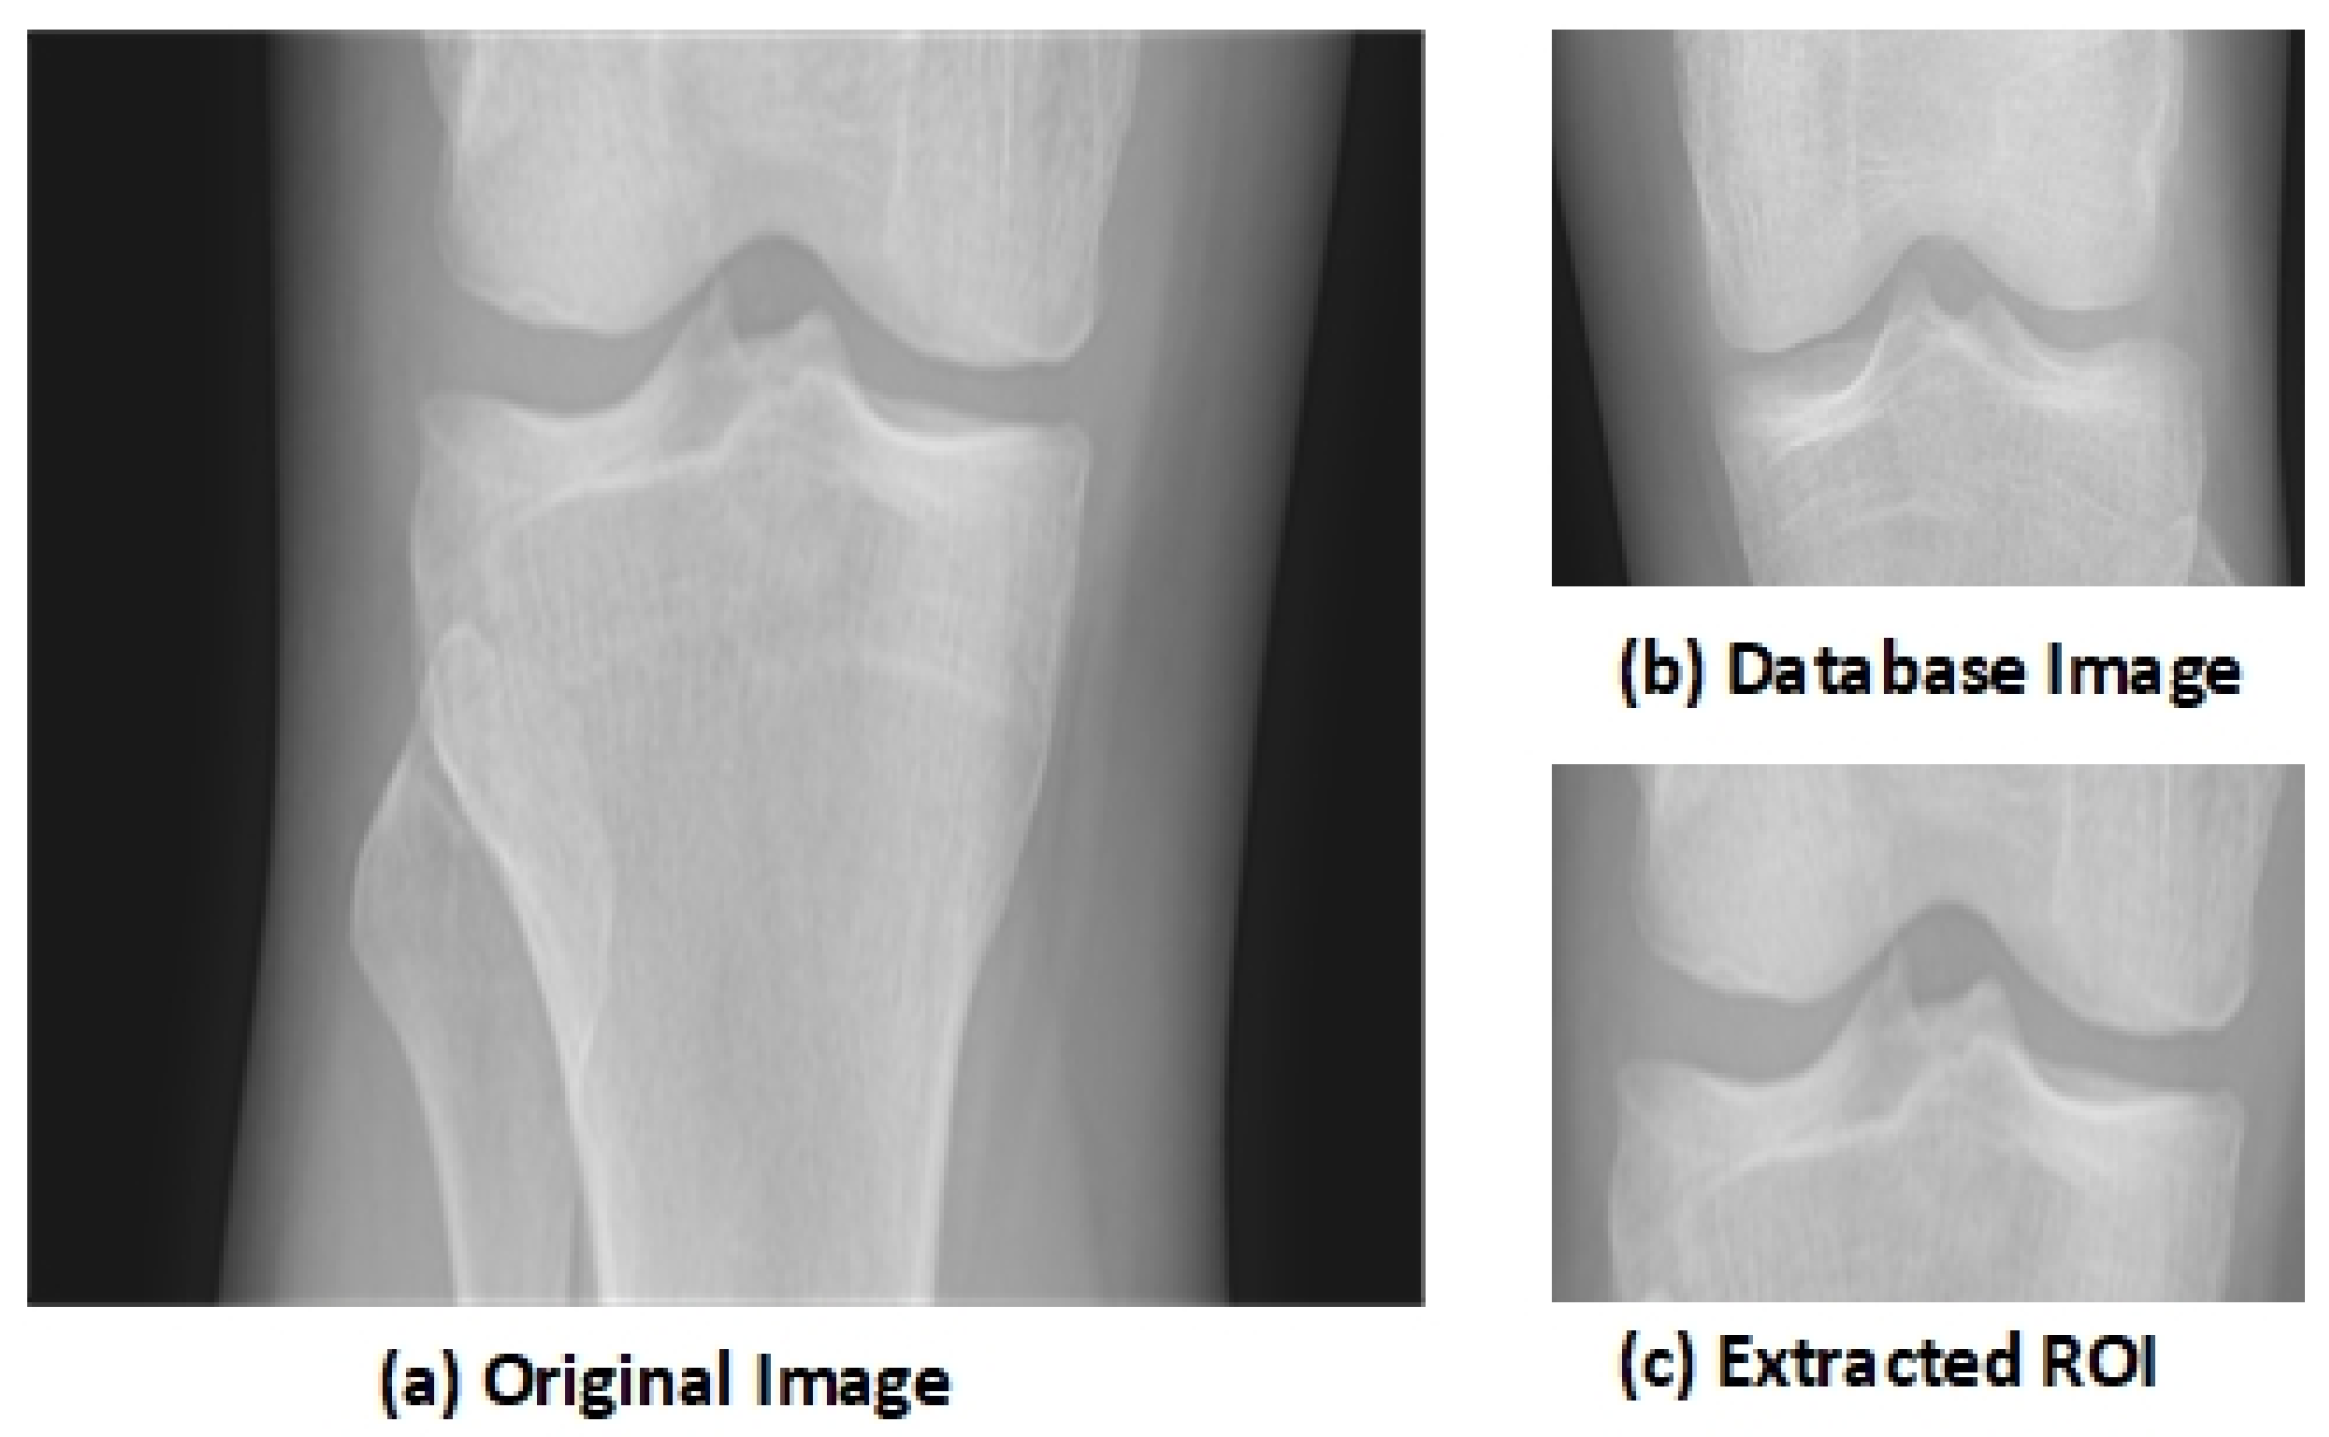

3.2. Region of Interest (ROI) and Segmentation